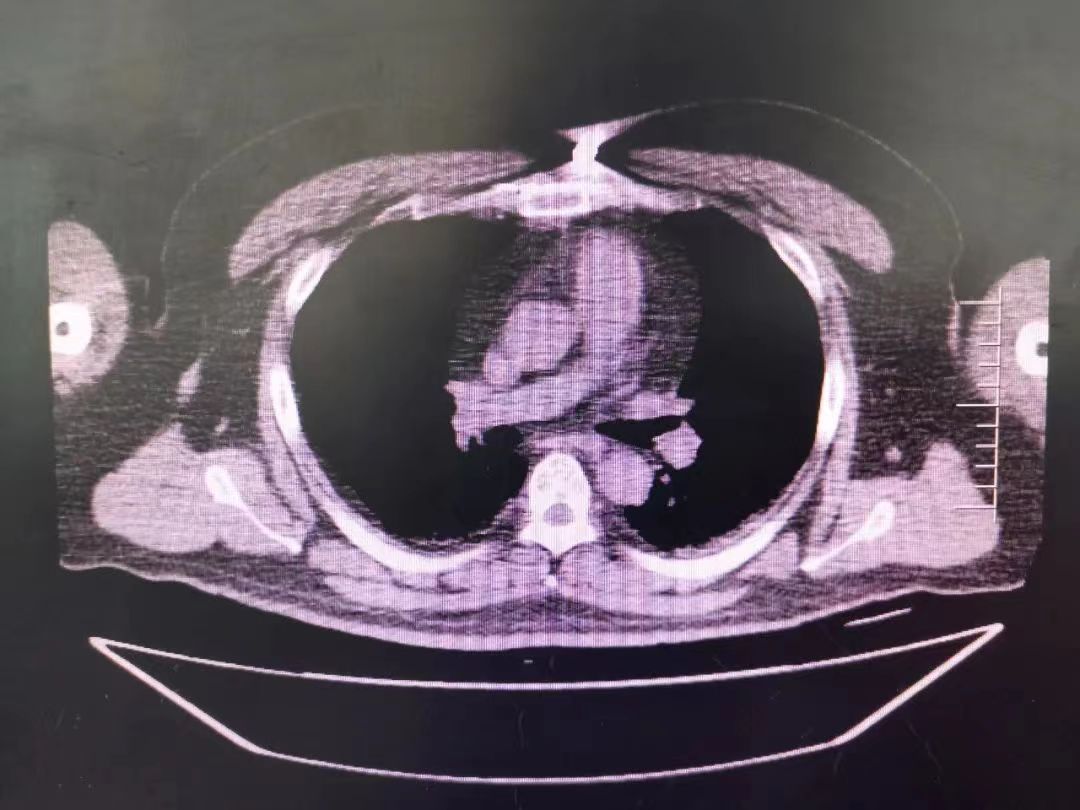

CT室門口,焦燥的家屬不停的走動著、等待著,看到醫(yī)生的到來,快速跑到醫(yī)生面前說:“醫(yī)生,快幫我看看,病人怎么樣”。陳醫(yī)生過去一看,一個體型偏胖的患者平躺在床上,一把剪刀齊根直插胸口觸目驚心,陳醫(yī)生不由眉頭一緊,轉(zhuǎn)身去看電腦CT影像 --剪刀斜著刺入胸骨,將胸骨完全穿透,刀尖距離心包約1-2mm,正下方是主動脈,大量心包積液?再一看,患者肥胖,脂肪組織多,不排除脂肪偽影??紤]患者血壓相對平穩(wěn),由于緊張導(dǎo)致心率快,立刻安撫患者,讓其保持安靜,盡量避免咳嗽,避免深呼吸和過多運(yùn)動。隨即撥通了武小剛主任的電話:“主任,這有一位患者,銳器刺傷不排除已經(jīng)損傷到心臟,病人目前血壓平穩(wěn)”“嚴(yán)密監(jiān)測患者病情變化,準(zhǔn)備急診手術(shù),我馬上到”武主任說。